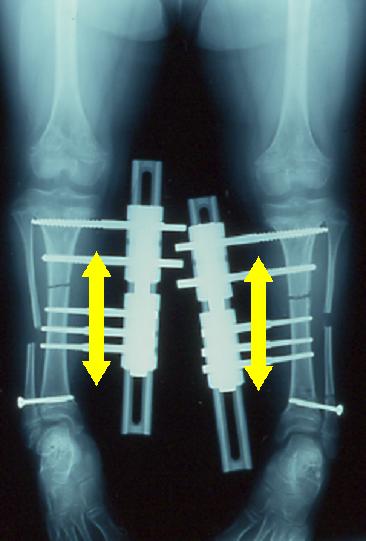

延長術後の経過